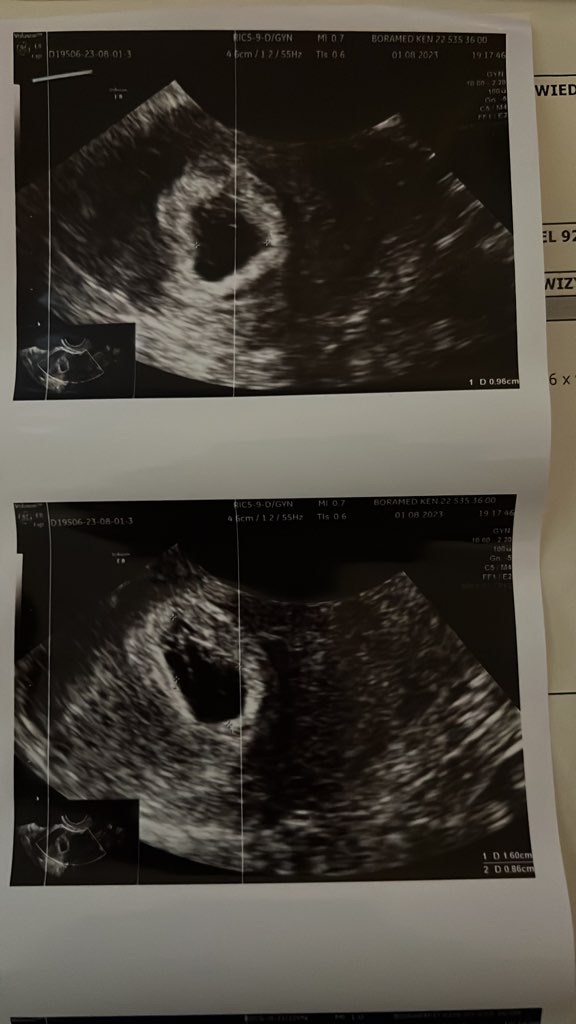

U mnie tak wyglada pęcherzyk ciążowy. Dwóch ginekologów zwróciło na to uwagę, że jest nieregularny kształt. W piątek byłam w szpitalu, byłam wtedy 6t6d i doktor zauważyła zarodek 2mm i wątpliwe tętno zarodka.@PepkaS a masz może zdjęcie z USG? Co to znaczy że nieregularny kształt? Bo mój w pierwszej ciąży i teraz jest w kształcie takiej fasolki.

Jutro idę do gin, więc zajrzy tam i zobaczymy, ale w piątek też mam wizytę w szpitalu. Ogólnie dostałam sygnał, żebym się nie nastawiała, może być tak, że zarodek się nie rozwinie

Czytałam tu na forum, że kobiety miały takie nieregularne pecherzyki i niektóre z nich donosiły ciąże i dzieciaczki są zdrowe. A tym, którym się nie udało nastąpiło poronienie.

Mój pęcherzyk też był taki nieregularny lekarz mówił że jest za mały, zarodek z sercem już był. I echo takie sobie, też mówił że częstotliwość bicia jako tako... Ten mój pęcherzyk przypominał jakby PolskeU mnie tak wyglada pęcherzyk ciążowy. Dwóch ginekologów zwróciło na to uwagę, że jest nieregularny kształt. W piątek byłam w szpitalu, byłam wtedy 6t6d i doktor zauważyła zarodek 2mm i wątpliwe tętno zarodka.

Jutro idę do gin, więc zajrzy tam i zobaczymy, ale w piątek też mam wizytę w szpitalu. Ogólnie dostałam sygnał, żebym się nie nastawiała, może być tak, że zarodek się nie rozwiniei nastąpi poronienie. Dlatego chodzę jak na tykającej bombie.